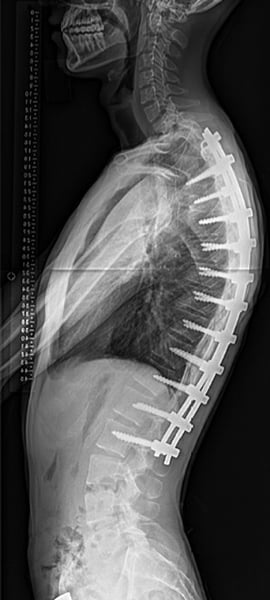

Radiographs of a patient with Scheuermann’s kyphosis who underwent corrective surgery (spinal fusion with instrumentation).

When surgery is indicated, as is often the case in Scheuermann’s kyphosis, an orthopedic surgeon will restore physiologic alignment to the spine by performing one or more of the following procedures: removing abnormal discs, fusing the affected vertebrae together, and placing instrumentation in the spine as needed to maintain correct posture while the vertebrae fuse together.

A posterior surgical approach (accessing spine from the back) is the most common method. However, patients with a large, rigid curve may also require an additional procedure with an anterior approach (through the chest).

With increasingly sophisticated surgical techniques and instrumentation, surgical treatment for kyphosis is easier to recover from than ever before. Patients who require only one posterior procedure (incision in the back) are up and out of bed the next day. Patients may not need to wear a brace following surgery. General anesthesia is used during these surgeries and hospitalization lasts between four to six days depending on the extent of surgery and age. Physical therapy after surgery is generally started once the bones have some time to heal (usually three to six months).

In patients with good bone quality, excellent results can be achieved. Success is defined as a solid fusion that reduces pain and in which the magnitude of the curve is decreased while maintaining a balanced spine.